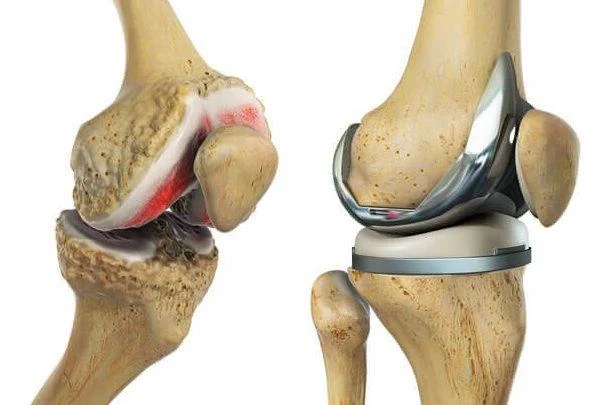

Total knee replacement (TKR) is a surgical procedure in which the damaged or worn-out surfaces of the knee are removed and replaced with components made of metal and plastic. These man-made components mimic the natural movement of a healthy knee, thereby relieving patients from pain, stiffness, and functional limitations.

- Removal of Damaged Surfaces: Using precise surgical tools, the surgeon cuts away the worn-out cartilage and bone from the femur (thigh bone), tibia (shin bone), and underside of the patella (kneecap). Special jigs and instruments help maintain correct alignment.

- Implantation of Prosthetic Components: The surgeon places metal caps on the femur and tibia, sometimes with bone cement. A plastic spacer is also inserted between them to allow smooth gliding. If needed, the back of the kneecap is also resurfaced with a plastic implant.